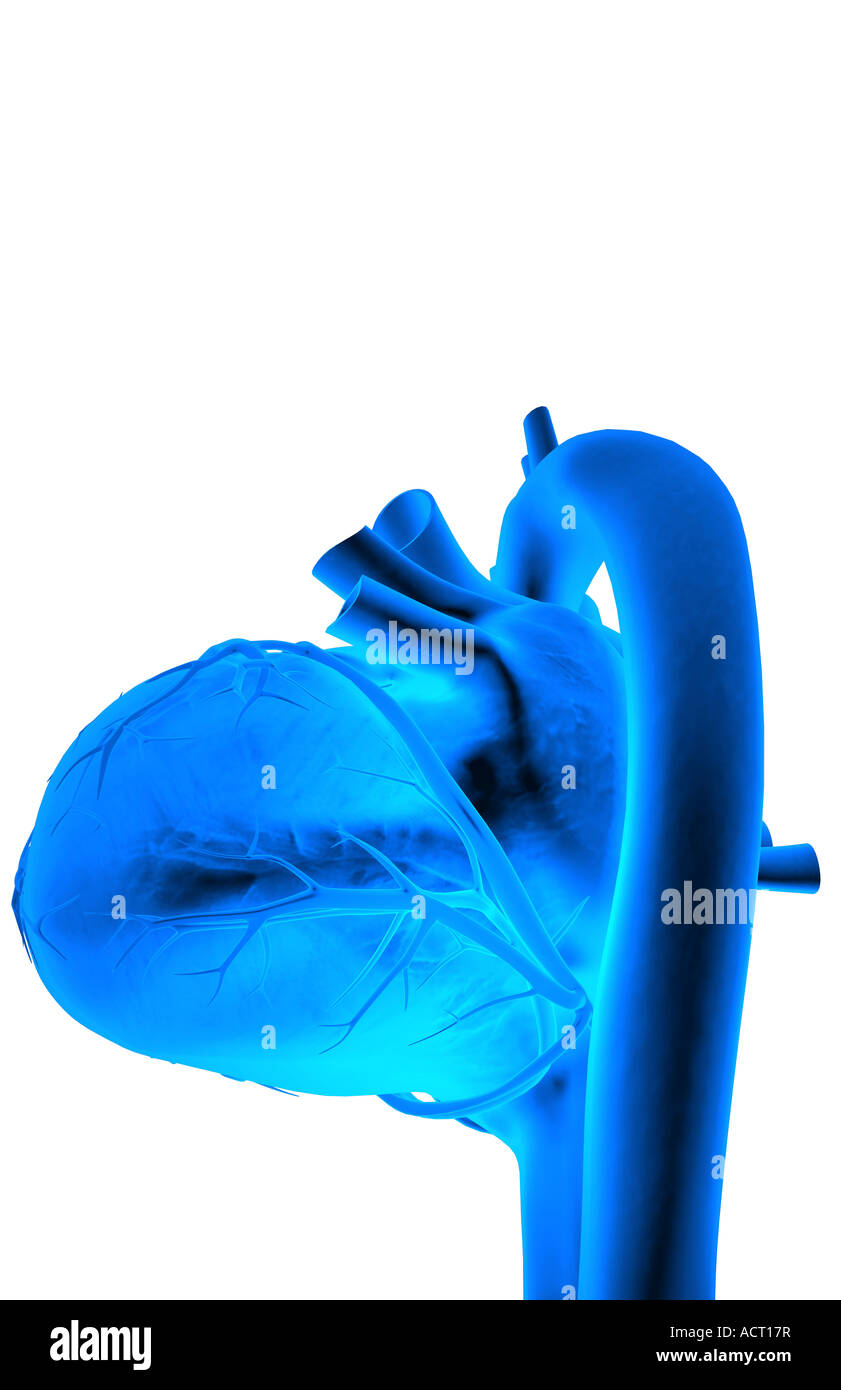

The coronary vessels of the heart Stock Photohttps://www.alamy.com/image-license-details/?v=1https://www.alamy.com/stock-photo-the-coronary-vessels-of-the-heart-13221802.html

The coronary vessels of the heart Stock Photohttps://www.alamy.com/image-license-details/?v=1https://www.alamy.com/stock-photo-the-coronary-vessels-of-the-heart-13221802.htmlRFACT17R–The coronary vessels of the heart